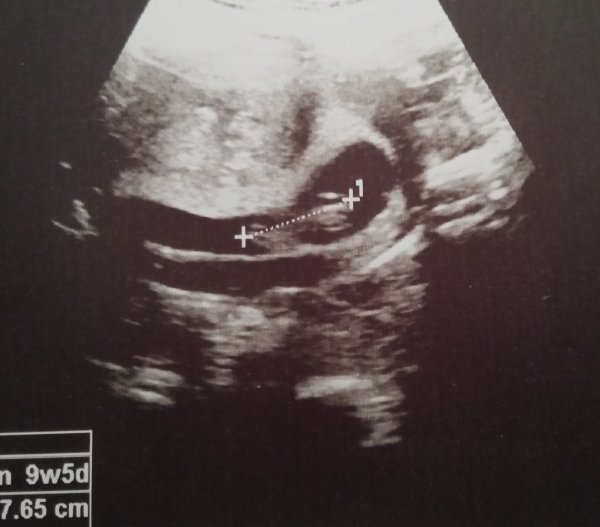

Bu görünüyor mu 9+5 bu hafta 11 olucam birtane daha yüklerim gidebilirsemResim bakmamız gereken kriterleri malesef karşılamıyor hayatım çok bulanık asla görünmüyor. Başka resim olduğunda yüklerseniz, tekrardan değerlendiririz.